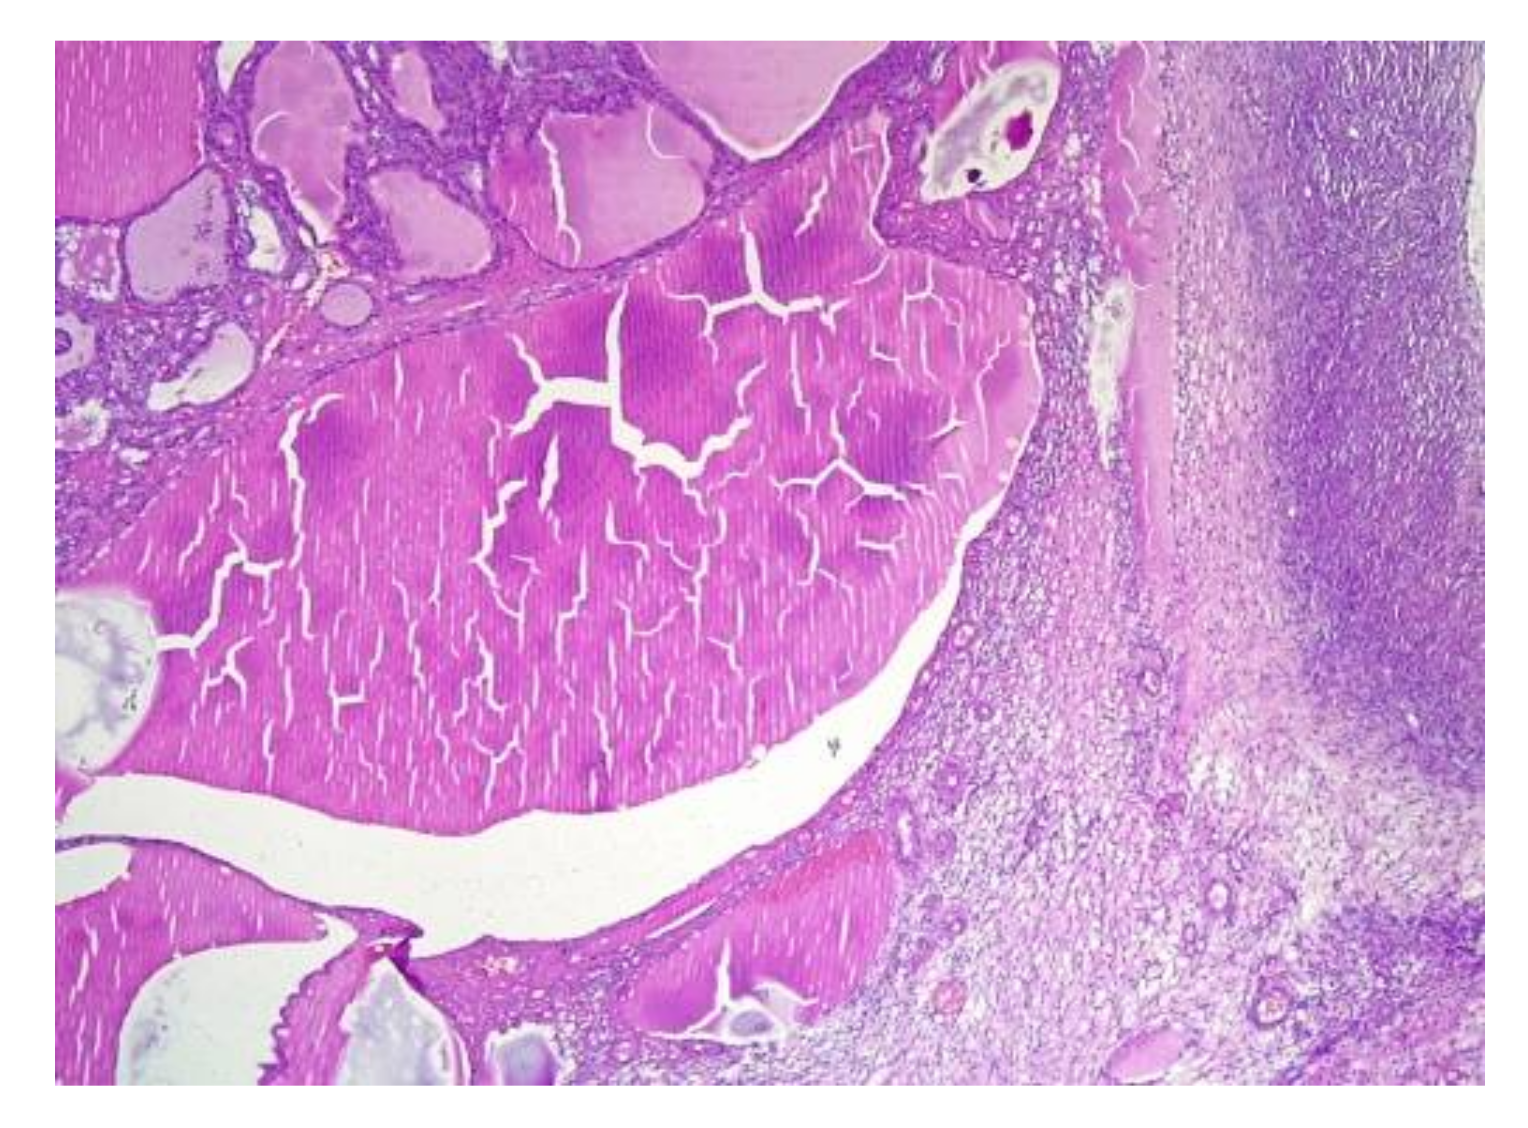

4.2. Histopathology Features